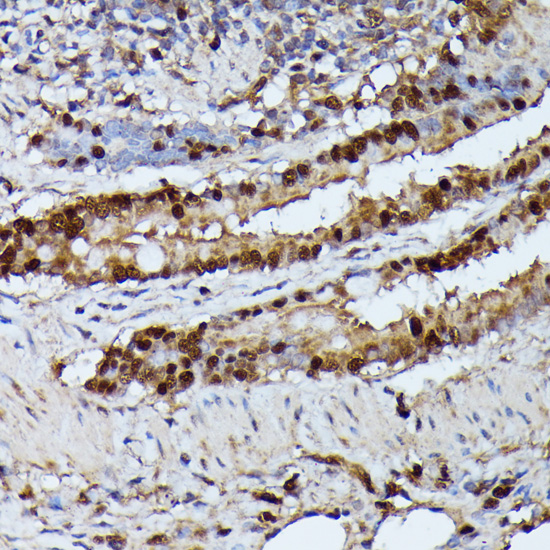

Immunohistochemistry of paraffin-embedded rat lung using GADD45A antibody at dilution of 1:100 (40x lens).

Immunohistochemistry of paraffin-embedded human thyroid cancer using GADD45A antibody at dilution of 1:100 (40x lens).

Immunohistochemistry of paraffin-embedded mouse liver using GADD45A antibody at dilution of 1:100 (40x lens).